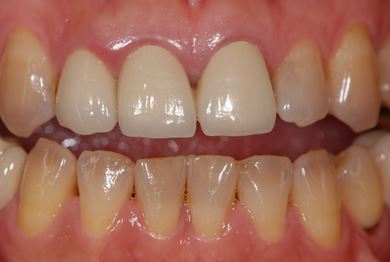

治療後

• 治療後